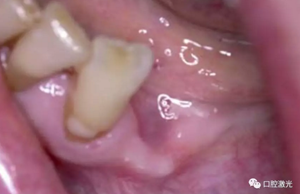

激光輔助治療術(shù)中

術(shù)后即刻,薄膜層的形成